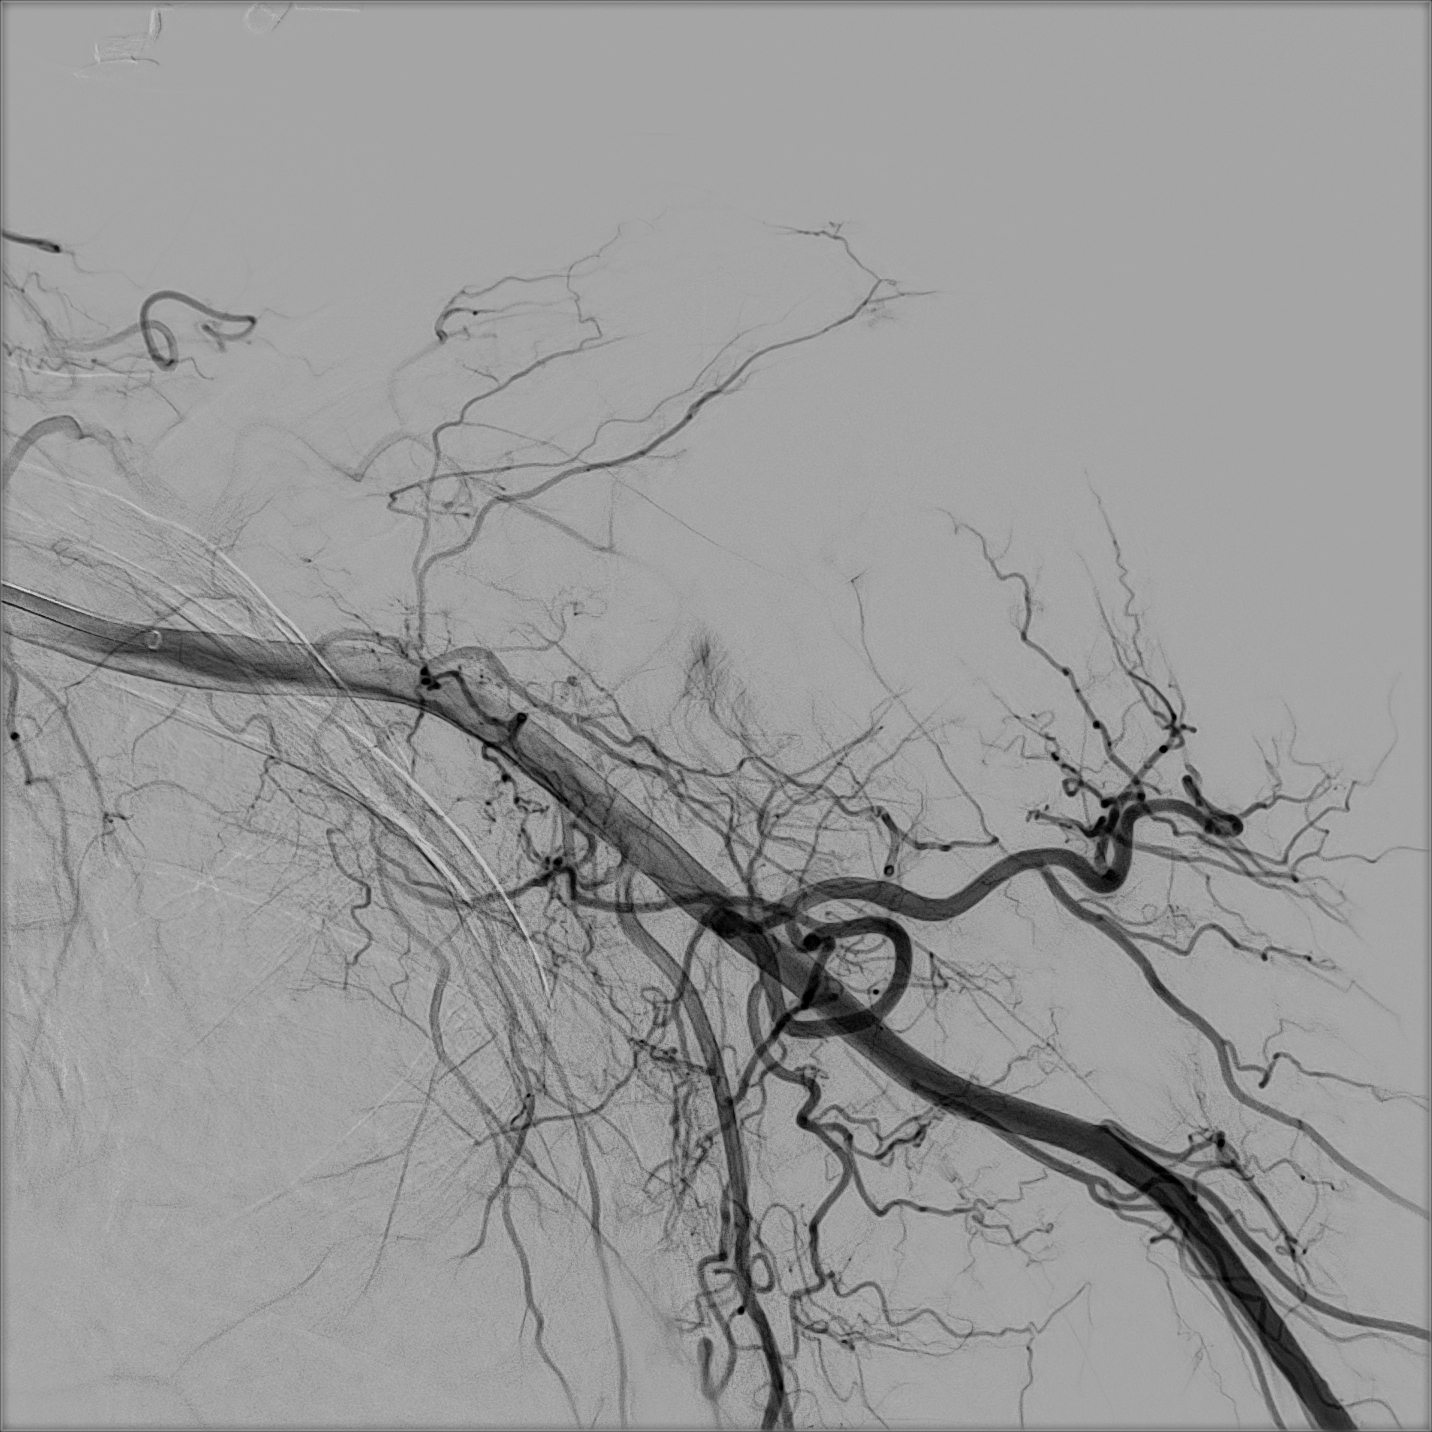

Could musculoskeletal embolization be the breakthrough chronic pain patients have been waiting for? This minimally invasive procedure is emerging as a promising treatment for conditions like osteoarthritis and tendinopathies. Learn how targeted embolization can reduce inflammation, improve mobility and offer relief when other therapies fall short.

Pelvic varicosities secondary to Pelvic Venous Insufficiency (PeVI) can cause chronic pelvic pain (CCP) with debilitating symptoms in women. Although various techniques and embolic agents have been reported, embolisation provides about 75% symptom relief, making it a minimally invasive treatment option.

Uterine Artery Embolisation (UAE) is one of the most valuable elective treatments that IRs can offer. However, the procedure has always suffered from a relative lack of awareness and exposure, leading to many women potentially missing out on finding out about it, or even worse not finding an IR that can perform it. Data to support safety and efficacy of UAE is abundant, and yet it seems that patient access remains problematic. Should the IR community be doing something different?

Endovascular management of vascular access is an exciting field that emerged as a valid option for hemodialysis patients extending from stenosis treatment, decloting salvage procedures, hemodialysis catheter insertion, and lately to percutaneous arteriovenous fistula creation.